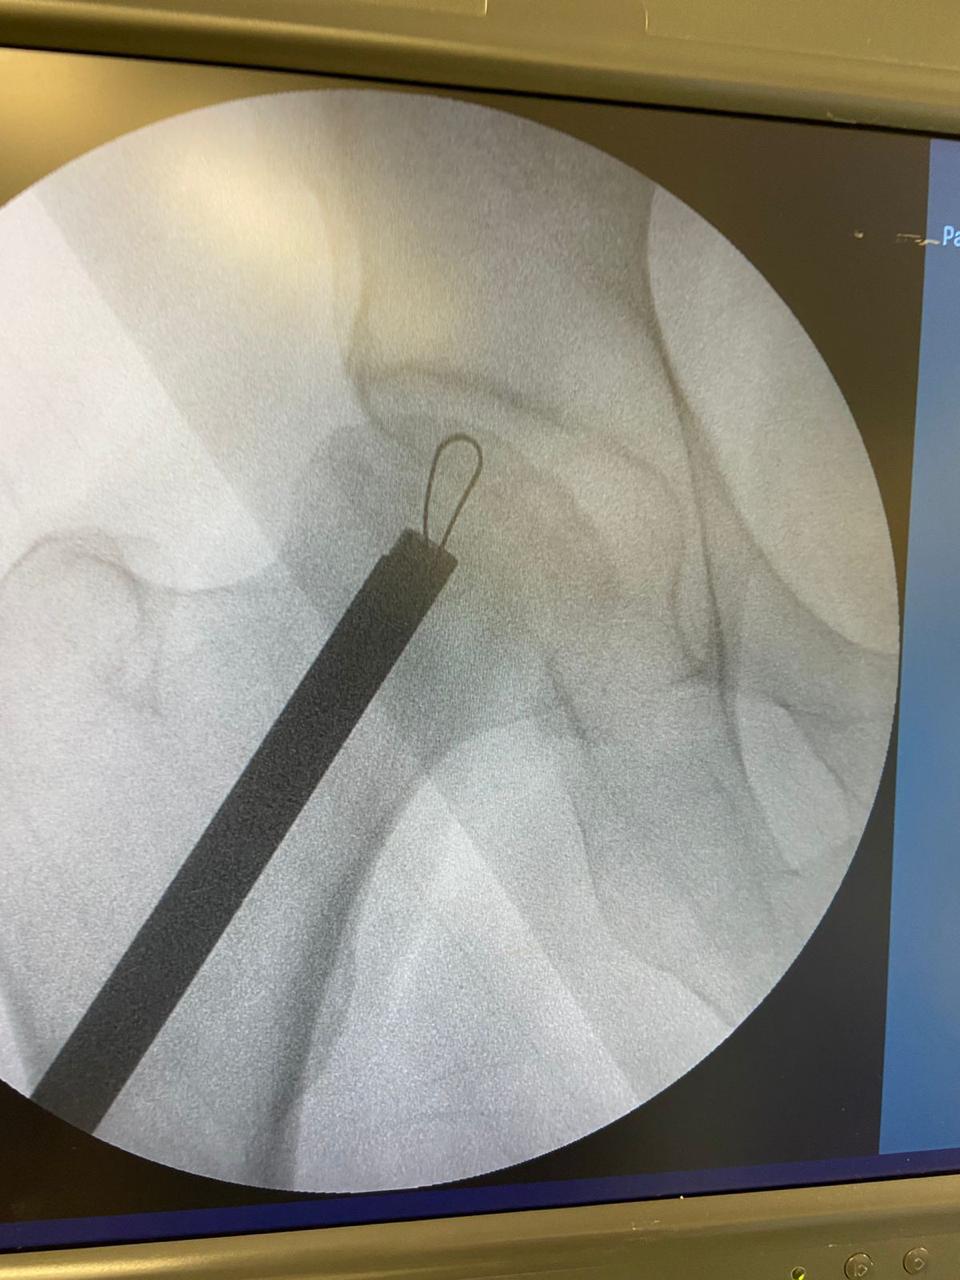

Precisão: A lâmina expansível descartável EasyCore Hip, feita em Nitinol, pode ser ampliada e retraída com facilidade até o raio de corte necessário para remover seletivamente o osso necrosado.

Descompressão do núcleo da cabeça femoral para o tratamento minimamente invasivo dos dois primeiros estágios (pré-colapso) da necrose avascular do quadril.

Descompressão de necrose avascular (estágios I e II) da cabeça femoral